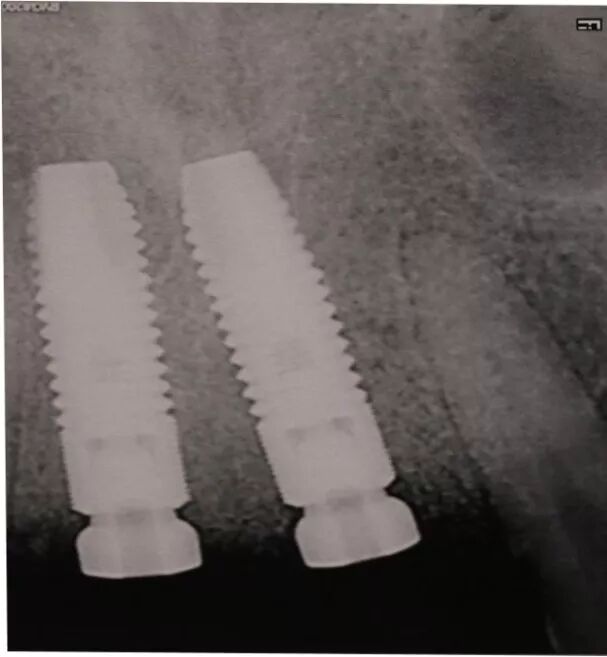

4.軟組織修復(fù)型材料在附著齦增厚術(shù)的應(yīng)用

軟組織修復(fù)型附著齦增厚術(shù)的應(yīng)用

牙周治療、拔牙后唇側(cè)

鄂側(cè)

骨缺損區(qū)域

使用鈦釘增加垂直骨高度

植骨并覆蓋GBR膜

二期植入種植體

覆蓋軟組織修復(fù)膜

5.0線縫合 唇側(cè)

術(shù)后四周? 顎側(cè)

唇側(cè)